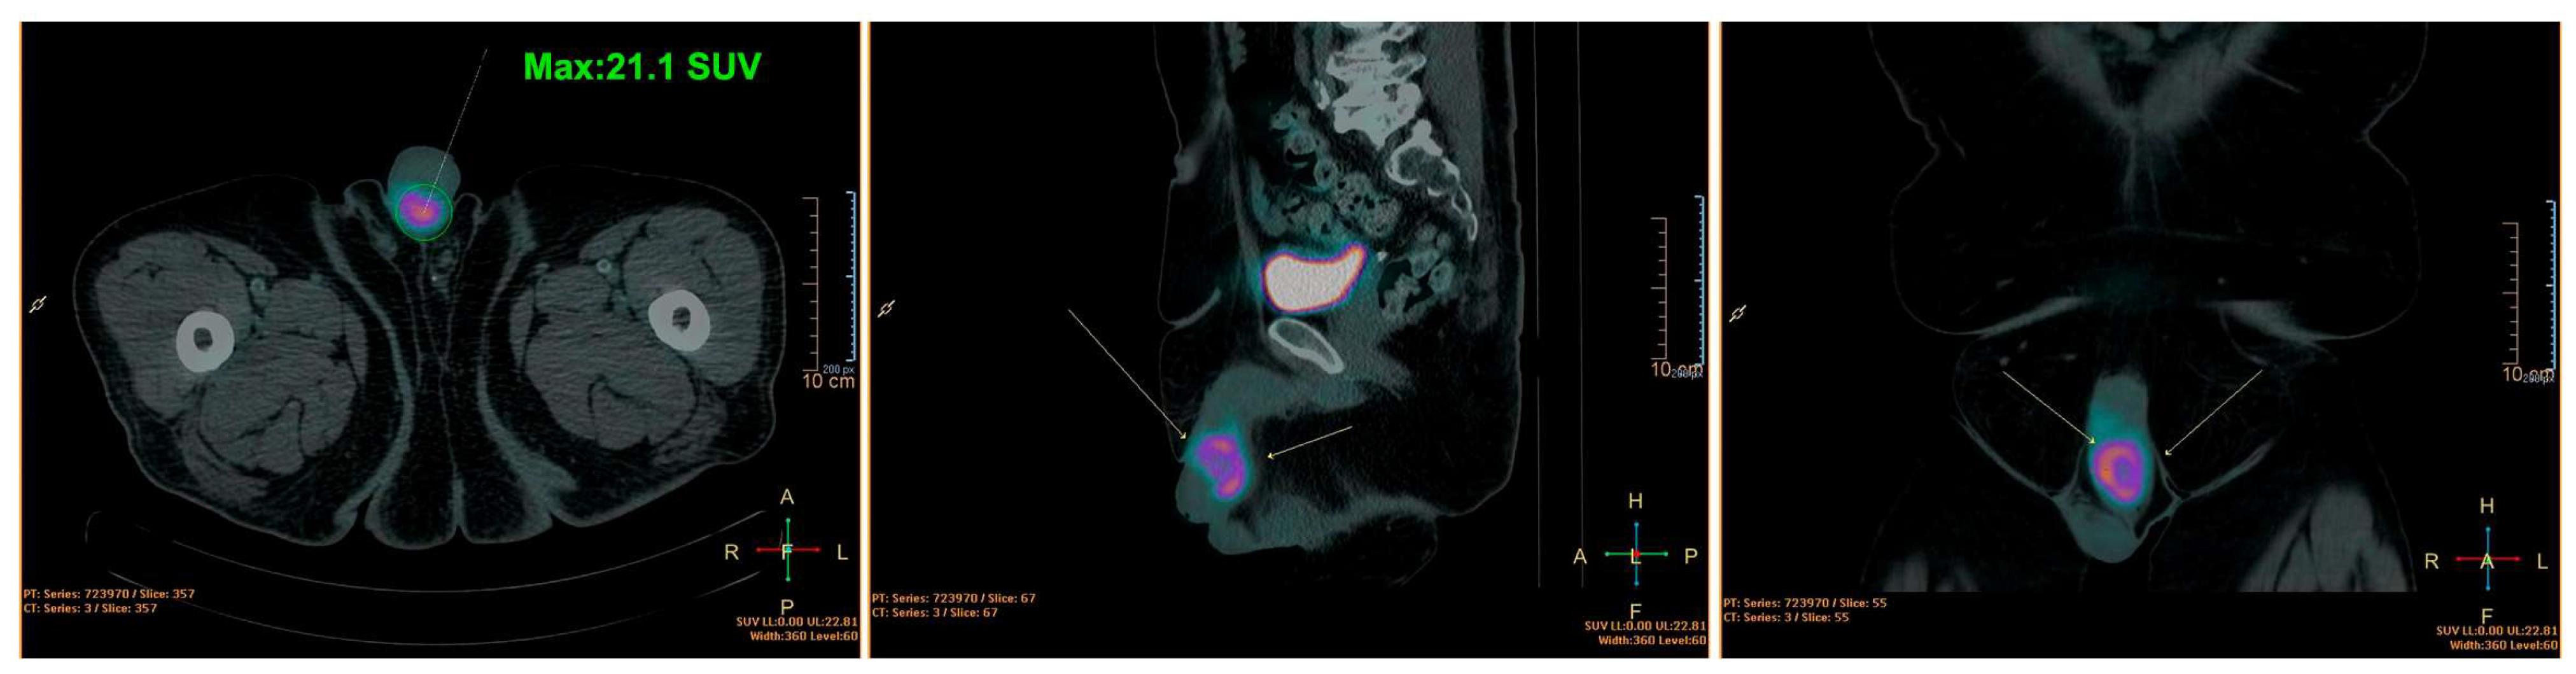

A 56-year-old male patient presented with a progressively growing lesion at the base of the penis. He has a medical history of diabetes and hypertension and a family history of lung cancer. On physical examination, a tumoral mass was identified within the penile body, originating at the junction of the glans and the body, extending to approximately 2 cm towards the pubic region (Figure 1). The patient underwent true-cut biopsy and the diagnosis was high-grade spindle cell sarcoma. Imaging tests revealed a heterogeneous mass in the middle third of the penis, adjacent to the right corpus cavernosum. This mass appeared predominantly hypoechoic and exhibited intense vascularization in color Doppler imaging, measuring 4.0 cm × 3.0 cm. Subsequent pelvic magnetic resonance imaging (MRI) revealed an expansive lesion with irregular, poorly defined contours located in the transition between the glans and the cavernous bodies. This lesion exhibited slightly heterogeneous contrast enhancement with pronounced hypo signal foci observed in the apparent diffusion coefficient (ADC) images, indicating high cellularity. The dimensions measured were 4.1 cm × 3.9 cm × 3.2 cm. In addition, a computed tomography scan of the pelvis revealed the presence of a heterogeneous expansive lesion located at the transition between the glans and cavernous bodies, measuring approximately 4.1 cm, which was consistent with a primary tumor site. The exam also indicated the presence of a small calcified nodule in the right upper lobe, measuring 0.3 cm. The liver appeared with normal dimensions, with a hypodense nodular image in the periphery of the hepatic segment V, measuring 1.3 cm of indeterminate appearance. A PET-CT scan further confirmed the presence of an abnormal 18-FDG concentration in the pelvic region, corresponding to a lesion in the penile body with a standardized uptake value (SUV) of 21.1. No other regions of abnormal 18-FDG concentration were identified in the other anatomical areas examined, confirming the absence of distant metastasis (Figure 1).

Figure 1. PET-CT showing the presence of an anomalous concentration area due to the lesion in the penile body. The colors indicate an anomalous concentration area of 18F-DG and correspond to a site of abnormal local cellular metabolic activity (active lesion).